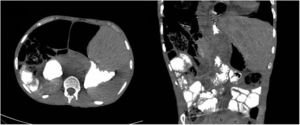

A 31-year-old man with severe intellectual disability came in with signs and symptoms of vomiting, constipation, abdominal distension and low-grade fever for the past two days. As bowel obstruction was suspected, abdominal computed tomography (CT) was ordered and showed gastric dilatation and a probable internal hernia (Fig. 1). Repeat CT with oral contrast to confirm and identify the site of obstruction showed the passage of contrast past the supposed obstruction to the small bowel loops, stomach decompression and the location of the liver in the left hypochondrium (Fig. 2).